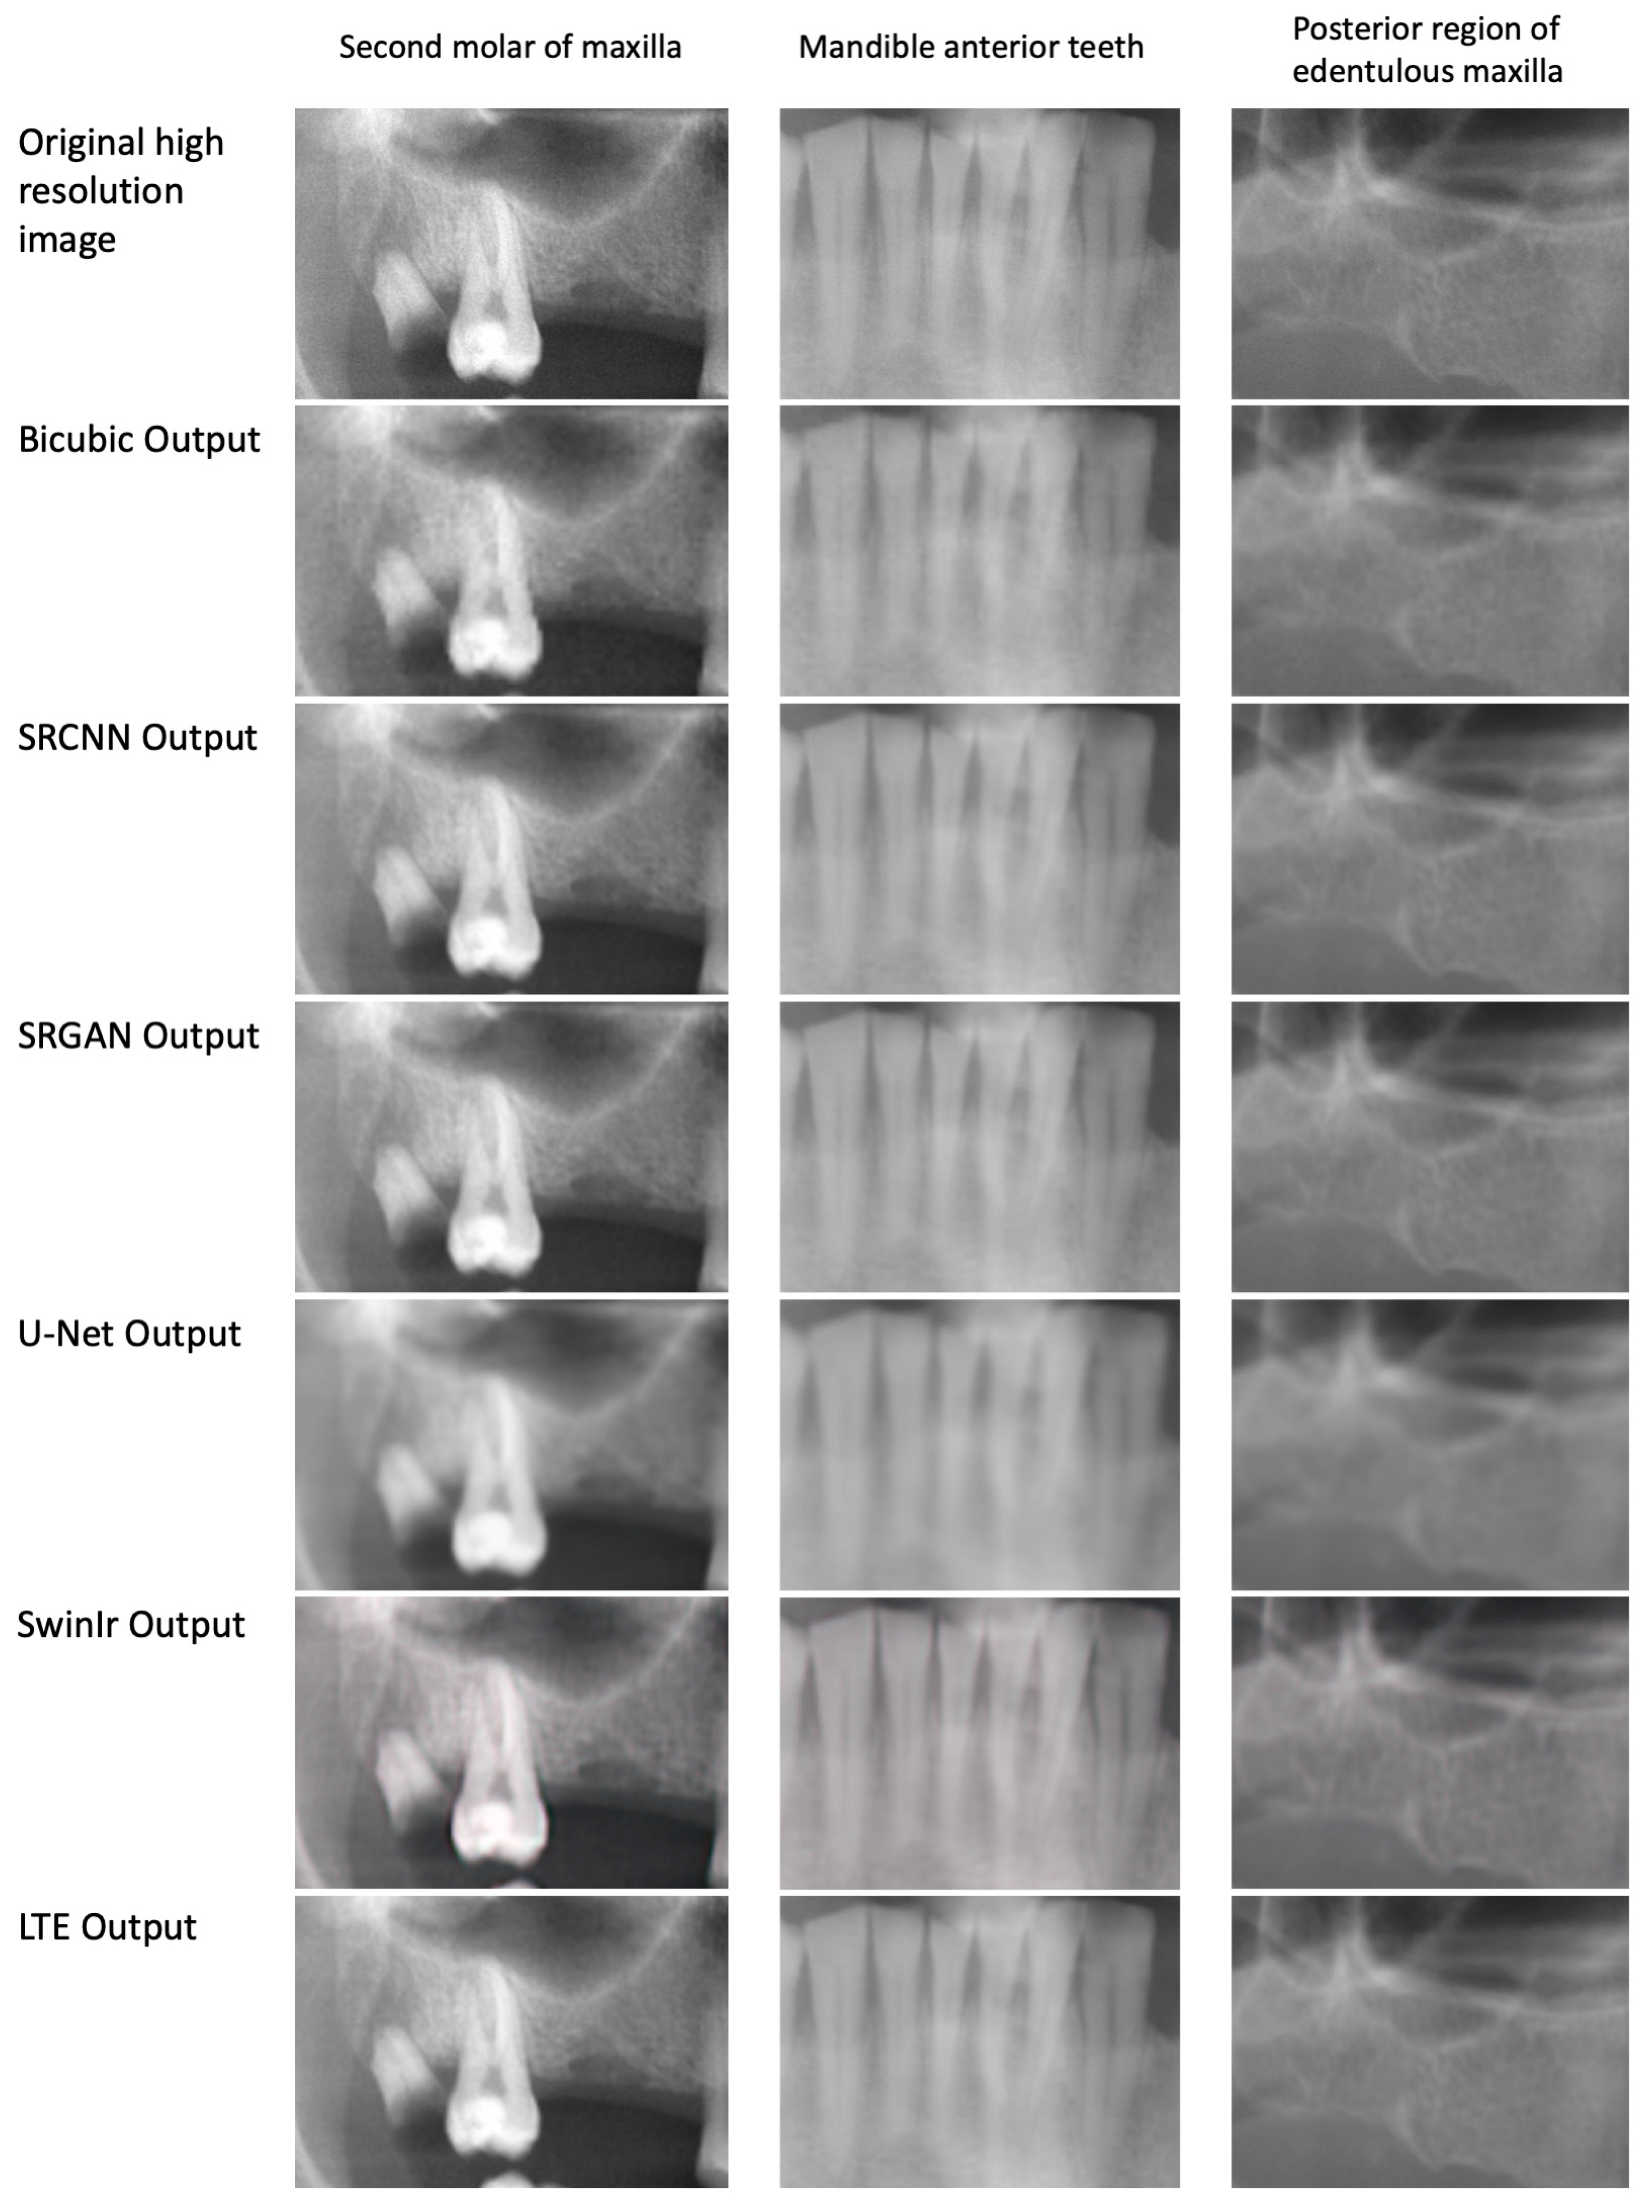

The sample output of the trained models is presented in Figure 1. Table 2 provides an overview of the performance of different models on the test set. Moreover, Table 3 presents the results of the statistical analysis of the models’ comparison. Regarding the MSE metric, SRCNN and LTE showed better performances with MSEs of 7.48 ± 0.30 and 7.42 ± 0.44, respectively (p < 0.001). Similarly, these two models outperformed others when assessing the PSNR (39.57 ± 0.16 and 39.74 ± 0.17, respectively) (p < 0.001). For SSIM, all models were found to have similar performance (0.916–0.919) except for SRGAN, which showed a poorer outcome with SSIM of 0.901 ± 0.005 (p < 0.001). All deep learning models outperformed the bicubic baseline when assessing MSE, PSNR, and SSIM (with all p < 0.001, except for SRGAN in PSNR, which was 0.046).

Figure 1.

Super-resolution with different approaches.

The results of the MOS evaluation are presented in Table 4. MOS was significantly higher for all SR compared with conventionally restored images. In bicubic images (Figure 1), it was impossible to see the root canals of the second molar, while, in HR and most SR approaches (except U-Net and, to some degree, SwinIR), these were visible.